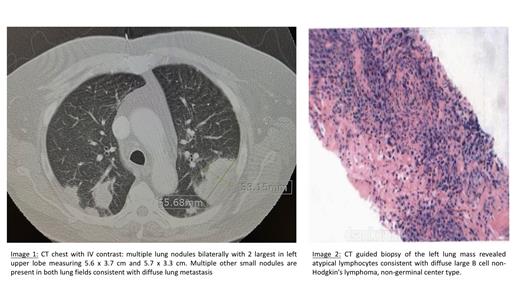

Upon presentation, work up showed mild anemia (Hb 11.1 g/dL). Cardiac work up for chest pain was unremarkable. Chest X-Ray revealed mass like opacities in each lung with largest in left mid lung measuring up to 6 cm. CT chest with IV contrast revealed multiple lung nodules bilaterally with 2 largest in left upper lobe measuring 5.6 x 3.7 cm and 5.7 x 3.3 cm. Multiple other small nodules are present in both lung fields consistent with diffuse lung metastasis. No lymphadenopathy was noted. (Image 1) PET CT scan was significant for bilateral FDG avid lung lesions. No evidence of other FDG avid disease.

CT guided biopsy of the left lung mass surprisingly revealed diffuse large B cell non-Hodgkin's lymphoma, non-germinal center type. (Image 1) Immuno-histochemistry showed atypical lymphocytes positively stained with CD20, BCL6, BCL2, PAX5 and MUM1. C-myc had 50% positivity. Ki67 had 90% proliferative index. FISH analysis was negative for MYC, BCL2 and BCL6; hence there was no double hit lymphoma detected.